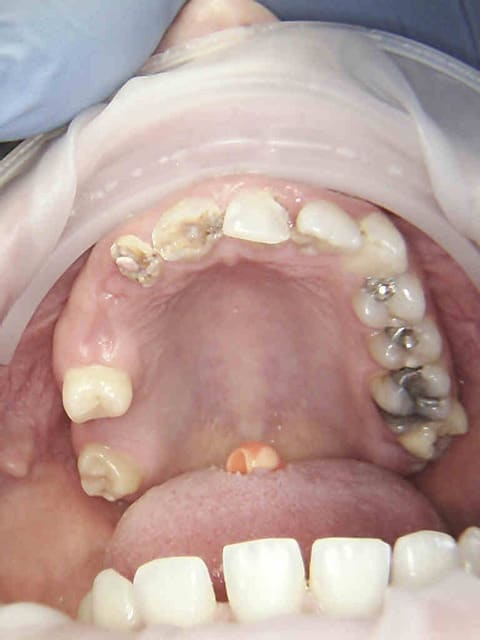

Et merde, encore raté pour les compos à 2 balles sous digue (pas indiqué) raté pour les onlays ceram (pas remboursés) sur 27 et 15 Reste plus que endo-ic-coiffe ou endo-sc33-coiffe en fonction de la mutuelle.))))

1 tf42wf - Eugenol

2 sltqnf - Eugenol

3 qcvnqa - Eugenol